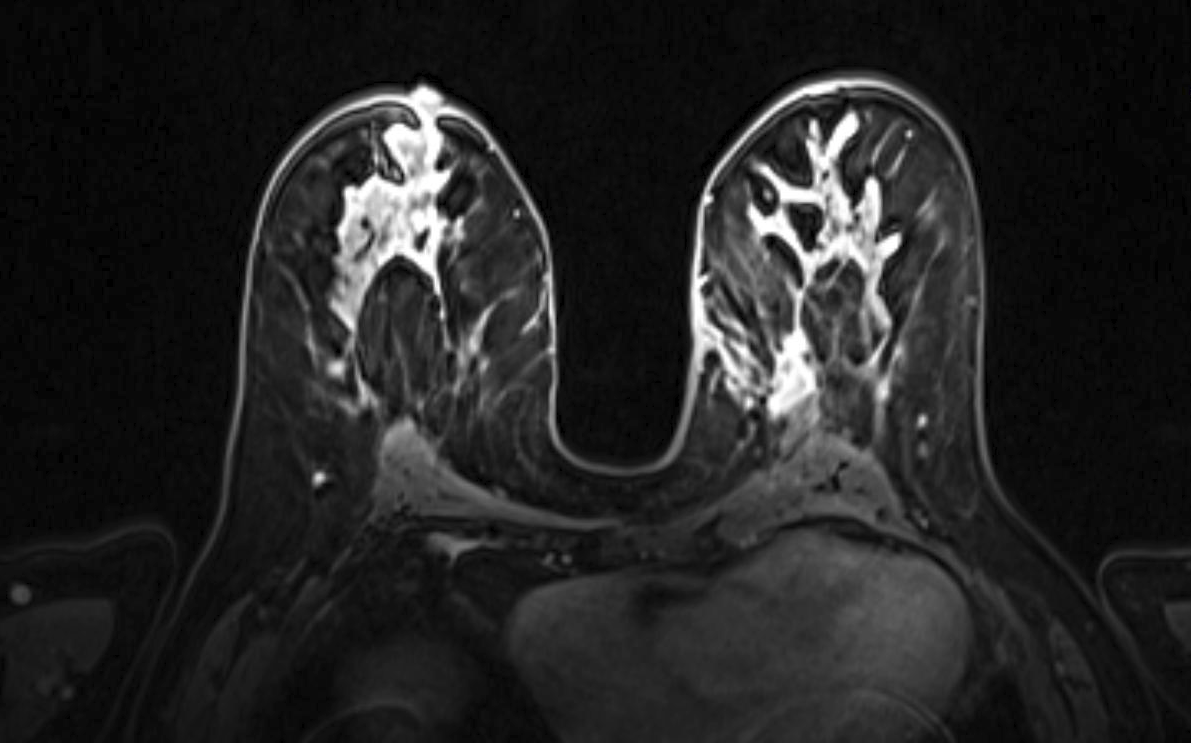

Magnetic resonance imaging (MRI) has been used as an adjunctive screening tool, mainly for women who may be at increased risk for the development of breast cancer. Example images of MRI are shown in fig. 5 with T1 contrast enhancement. MRI for screening has not been very popular in women with average risk due to concerns about the low specificity leading to additional biopsies, time and cost of technology [26]. Breast MRI sensitivity values reported in high risk screening studies range from 93% to 99%. Despite its high sensitivity, breast MRI has been reported to have variable specificity, ranging from 50% to 85% [27]. These number of sensitivity and specificity depends on the type of tumor, size of tumor, age of patient, and where it is localised.